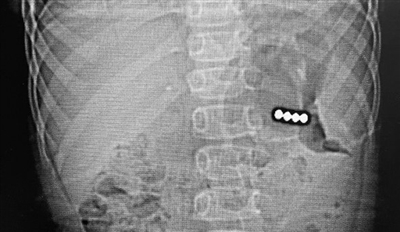

患儿的透视片显示四颗磁力球聚集在一起。

早报2月2日讯 近日,4岁的洋洋(化名)在玩耍时不慎被汽车碰倒,可没想到在当地医院检查时,除了因碰倒造成的皮外伤,竟“意外”发现——洋洋的肚子里有金属样的异物。转诊至青岛妇女儿童医院就医,通过腹部CT、消化内镜探查,救治人员发现磁力珠停留在患儿胃部,已经穿透胃壁,必须尽快手术。

小儿普外科团队立刻为洋洋进行急症手术,4颗磁力珠全部取出,患儿已康复出院。